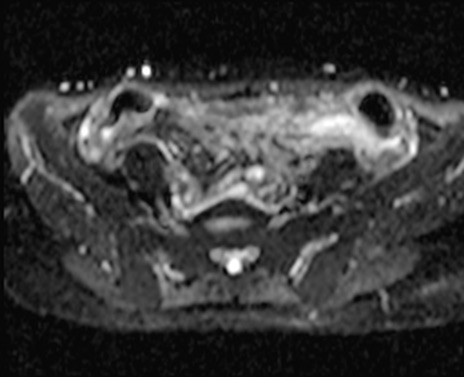

MRI(4日後)